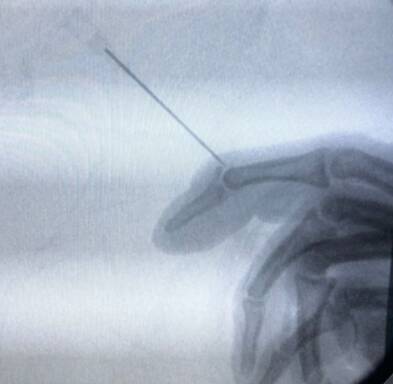

第一枚克氏针